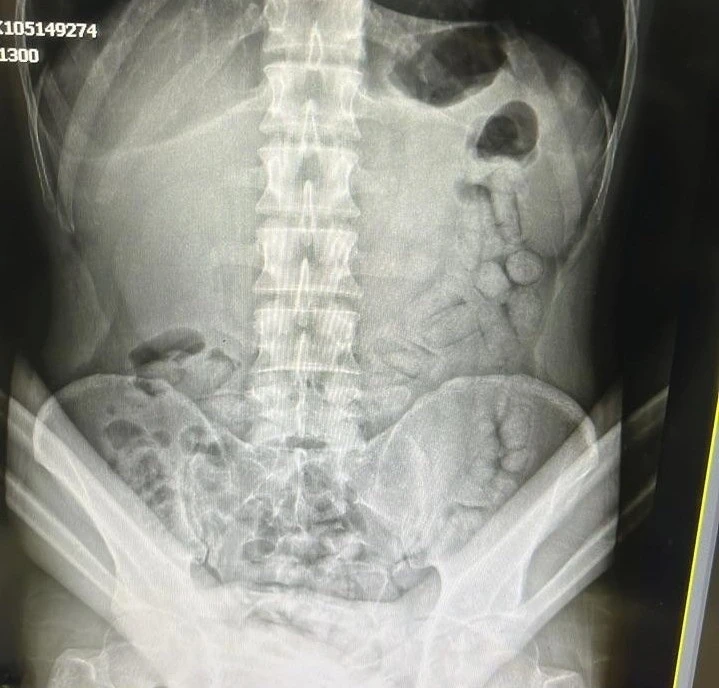

Adli makamların talimatı üzerine Gümüşhane Devlet Hastanesine götürülen şahsa yönelik iç beden muayenesinde bağırsaklarında 55 adet kapsül olduğu tespit edildi. Hastanede yapılan müdahalenin ardından şahsın bağırsaklarından çıkarılan kapsüllerin içerisinde toplamda 317,46 gram metamfetamin ele geçirildi.